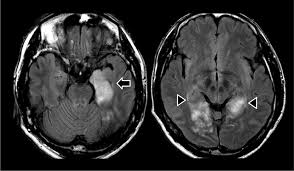

Hsv Encephalitis Mri Radiopaedia - Herpes Encephalitis Ct Scan Ct Scan Machine - It is a common finding on brain mri and a wide range of differentials should be considered 1.. Two subtypes are recognized which differ in demographics, virus, and pattern of involvement. 10 public playlist includes this case The changes spare the basal ganglia, a feature which is helpful in distinguishing an mca infarct with hemorrhagic transformation from herpes simplex encephalitis. Radiopaedia is free thanks to our supporters and advertisers. The changes spare the basal ganglia, a feature which is helpful in distinguishing an mca infarct with hemorrhagic transformation from herpes simplex encephalitis, the diagnosis in this case.

It is usually bilateral but asymmetrical. Hsv encephalitis | radiology case | radiopaedia.org. Note the high signal in the caudate heads and putamen on flair. Hypertrophic pachymeningitis is a condition where there is localized inflammatory thickening of the dura. For a general discussion, and for links to other system specific manifestations, please refer to the article on coccidioidomycosis. Radiopaedia is free thanks to our supporters and advertisers. Reference osborn a, et al. The changes spare the basal ganglia, a feature which is helpful in distinguishing an mca infarct with hemorrhagic transformation from herpes simplex encephalitis, the diagnosis in this case.

Two subtypes are recognized which differ in demographics, virus, and pattern of involvement. Become a gold supporter and see no ads. Bilateral temporal lobe t2 hyperintensity refers to hyperintense signal involving the temporal lobes on t2 weighted and flair imaging. Hypertrophic pachymeningitis is a condition where there is localized inflammatory thickening of the dura. Limbic encephalitis, mca ischaemia, tumours, effects of seizures) hyperintense t2 signal in the medial temporal lobes, inferior frontal lobes and insula basal ganglia are usually spared Reference osborn a, et al. Given the history of fever and seizures coupled with the mri findings of bilateral mesial temporal lobe changes, herpes encephalitis requires clinical consideration. The changes spare the basal ganglia, a feature which is helpful in distinguishing an mca infarct with hemorrhagic transformation from herpes simplex encephalitis, the diagnosis in this case. Mri demonstrates extensive edema in the right temporal lobe with areas of intrinsic high t1 signal, in keeping with hemorrhage. It is estimated to occur in ~2% of pati. The differential diagnoses include limbic encephalitis (paraneoplastic), gliomatosis cerebri, and status epilepticus. It is reasonable to obtain an mri when patients are asymptomatic to ensure that no other abnormality is present which may be causing a recurrent chemical meningitis (e.g. Axial t2 prominent swelling, increase t2 signal involving the left temporal lobe and insular cortex.

Axial t2 prominent swelling, increase t2 signal involving the left temporal lobe and insular cortex. Two subtypes are recognised which differ in demographics, virus, and pattern of involvement. Multilocularis.the larval stage is the cause of hydatid disease in humans 1. Cerebral malaria is a rare intracranial complication of a malarial infection. The changes spare the basal ganglia, a feature which is helpful in distinguishing an mca infarct with hemorrhagic transformation from herpes simplex encephalitis, the diagnosis in this case.

Mri demonstrates extensive edema in the right temporal lobe with areas of intrinsic high t1 signal, in keeping with hemorrhage. Become a gold supporter and see no ads. For a general discussion, and for links to other system specific manifestations, please refer to the article on coccidioidomycosis. This patient went on to have hsv encephalitis proven on csf pcr. This patient went on to have hsv encephalitis proven on csf pcr. Spinal hydatid disease is an uncommon manifestation of hydatid disease, caused by the larval stage of echinococcus granulosus, or less commonly e. Given the history of fever and seizures coupled with the mri findings of bilateral mesial temporal lobe changes, herpes encephalitis requires clinical consideration. Multilocularis, and describes a spectrum of disease involving the spinal cord, the spine, or both. Herpes simplex encephalitis radiology case radiopaedia mri demonstrates extensive edema in the right temporal lobe with areas of intrinsic high t1 signal, in keeping with hemorrhage. Hsv encephalitis | radiology case | radiopaedia.org. Two subtypes are recognised which differ in demographics, virus, and pattern of involvement. It is estimated to occur in ~2% of pati. Reference osborn a, et al.